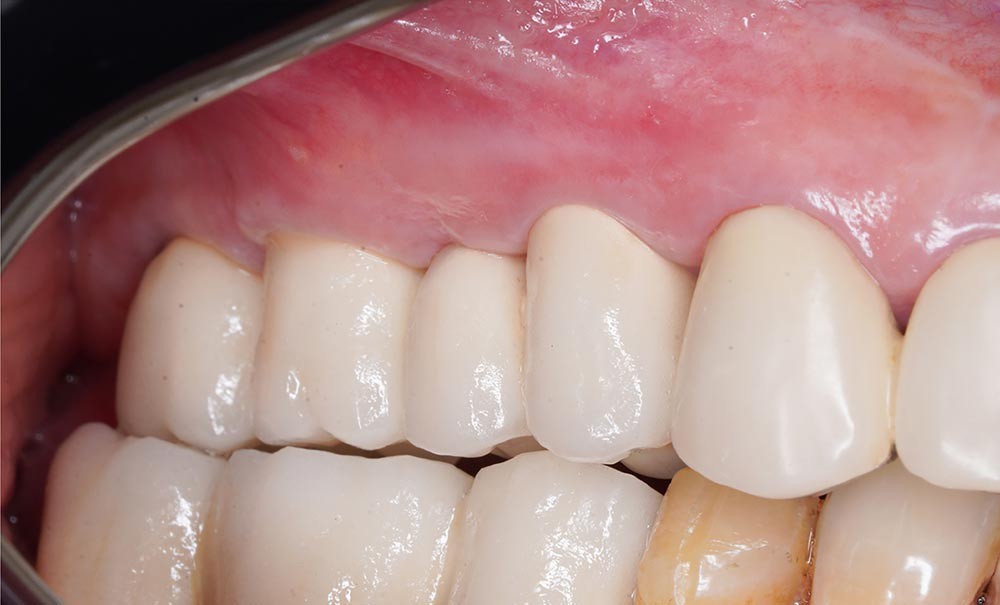

Une patiente de 52 ans en bonne santé, non fumeuse, a subi une augmentation osseuse et une greffe sinusale avec xénogreffe et membrane de collagène résorbable au niveau du maxillaire droit. Une chirurgie implantaire a été réalisée 9 mois plus tard et, après une période d’ostéointégration de six mois, les vis de cicatrisation ont été placées. Aucune des interventions chirurgicales n’a entraîné de complications. La patiente a conservé ces vis de cicatrisation pendant 6 semaines. Le praticien a ensuite pris une empreinte numérique et a opté pour des piliers personnalisés en titane et une restauration métallo-céramique scellée. Immédiatement après le scellement des restaurations, lors du même rendez-vous, le praticien a observé une suppuration provenant du sillon adjacent à l’implant 16 (fig. 1a).

Quatre mois après la suppuration initiale, une fistule est apparue à l’apex de l’implant 16 (fig. 2a). Cette fois, l’examen CBCT a révélé une résorption osseuse considérable (fig. 2b à d). Une chirurgie exploratrice a donc été décidée.